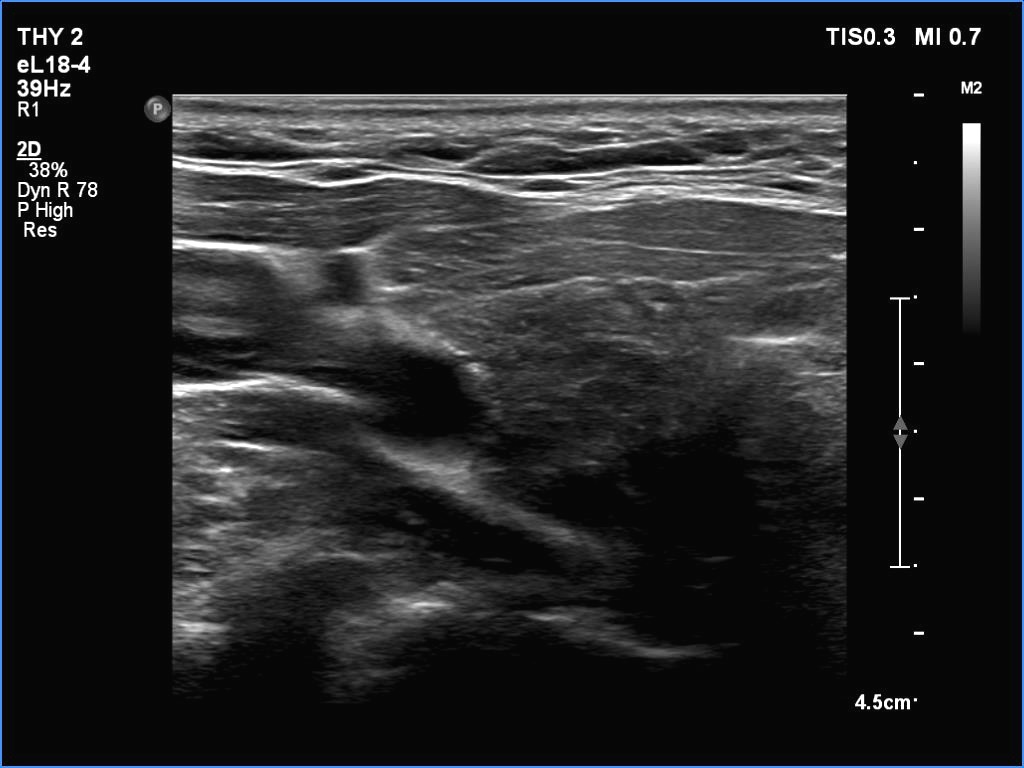

Ultrasonography. The thyroid was partly minimally/moderately, partly very hypoechoic. There was a nodule in the middle of the left lobe. It was lighter than the extranodular part but darker than a normal, healthy thyroid.